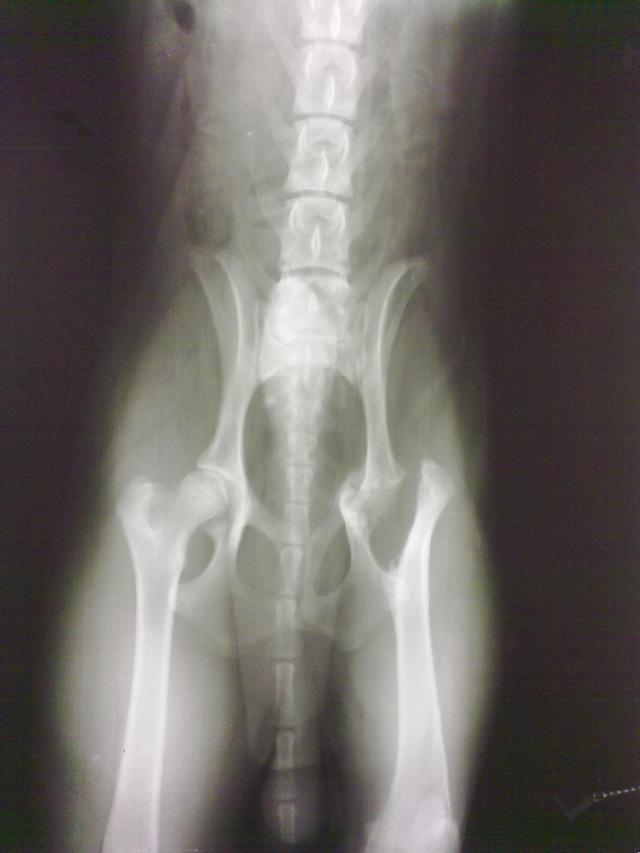

A lap rövid címe: http://allatok.info/animal.php?a=10380773 | Azonosító: | 3049 | Aktuális életkor: | 17 év 3 hónap | | Név: | Pracli | Befogadás dátuma: | 2009-06-22 | | Fajta: | bobtail, boxer, vizsla keverék | Elvihető ekkortól: | bármikor | | Nem: | fiú | A programba kerülés dátuma: | 2009-06-23 | | Ivartalanítva: | igen | Kennel száma: | | | Méret: | közepes | Embereket szereti: | igen | | Szőr jellege: | közepes | Gyerekeket szereti: | igen | | Szőr színe: | trikolór | Fiúkutyákkal barátságos: | igen | | Szobatiszta: | igen | Lánykutyákkal barátságos: | igen | | Javasolt tartás: | lakásban és kertben is | Cicákkal barátságos: | igen | | Ismertetőjegy: | !! Frissen műtött lábú, műtét után került utcára!! szálkás szőrű erdélyi vizsla és boxer keverék leginkább, | | Befogadás körülményei: | Fóti úti benzinkútra ment menedékért, ott etették, értesítettek, igyekeztek gazdáját meglelni - köszönet a Fóti úti benzinkutasoknak!! | | Megjegyzés: | Eredeti vagy új gazdiját keresi Pracli, ez a barátságos, szobatiszta, minden emberhez, gyermekhez kedves, kan és szuka kutyusokkal játékos, cicákat nem bántó, 8 hónapos kb. 06. 15. körül lábán műtött kan kölyök. A műtét oka baleset lehetett, csípője tört el, combcsontjából vágni kellett. Már nincs fájdalma, picit sántít, de gyorsan és szívesen szalad, labdázik társaival.